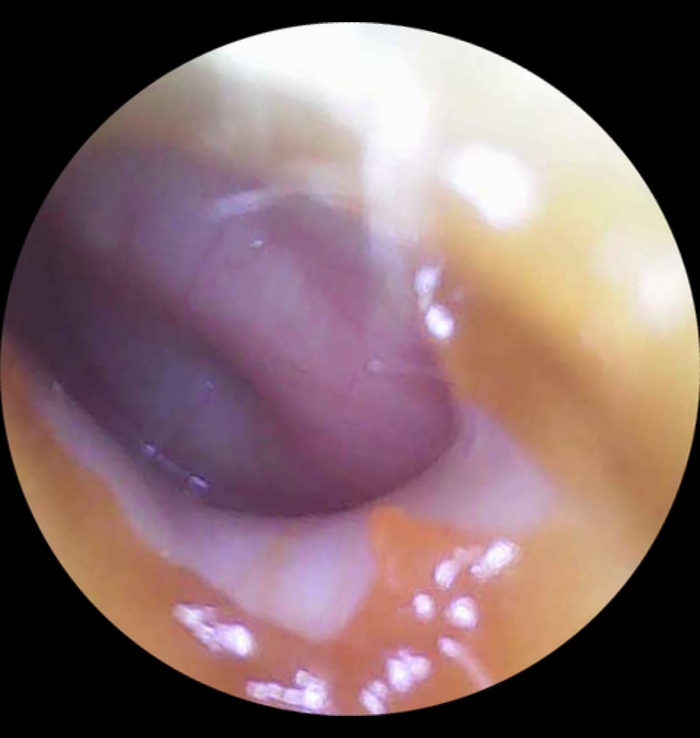

На следующий день оба уха в отличном состоянии

1/2

Голубое также световой конус. Зеленые линии - границы прозрачной жидкости в ухе, этап восстановления. Это называется «экссудативный средний отит» и точно не требует антибиотиков.